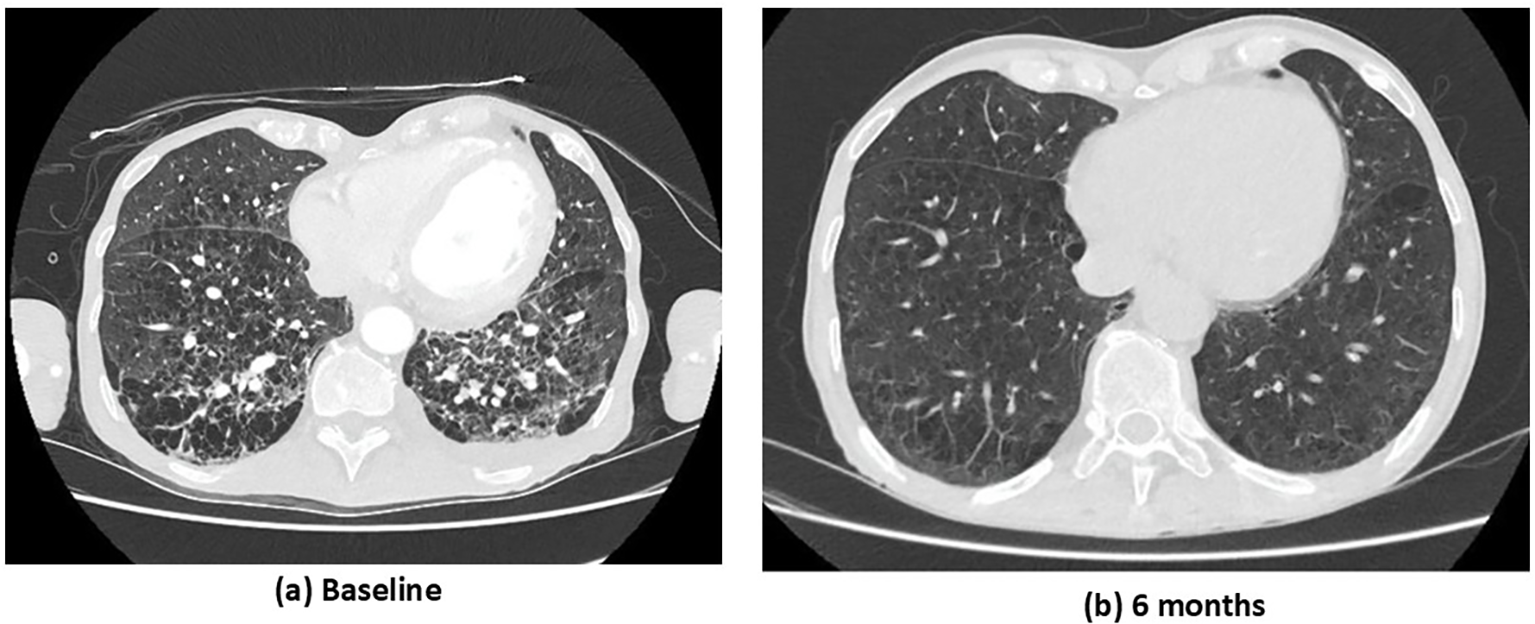

Kidney biopsy revealed pauci-immune necrotizing crescentic glomerulonephritis with severe acute tubular injury: 10% cellular crescents, 90% normal glomeruli, 10% interstitial fibrosis, and no global sclerosis (Figures 1A, B). Immunofluorescence evaluation showed mild IgM (1+/2+) positivity, while IgG, IgA, C3, C1q, C4, and κ and λ light chains were negative. The biopsy was classified as focal class by Berden’s classification and moderate risk according to the ANCA Kidney Risk Score (7). Systemic evaluation demonstrated multisystemic disease. High-resolution CT chest study revealed a usual interstitial pneumonia (UIP) pattern with extensive bilateral fibrotic thick-walled lesions and pleural-based honeycombing (Figure 2A). ENT involvement was indicated by thickening of the sphenoid sinuses and partial opacification of the right mastoid air cells on CT. On admission, serum troponin levels were markedly elevated (645 pg/mL) in the absence of chest pain. Transthoracic echocardiography revealed severely reduced left ventricular ejection fraction (LVEF 20%) with diffuse wall hypokinesia (compared with LVEF 65% ten days earlier). Coronary angiography excluded significant coronary artery disease. Cardiac magnetic resonance imaging (MRI) demonstrated myocarditis, with mid-septal interstitial fibrosis on T1 mapping and myocardial edema on T2 mapping. Clinical examination additionally revealed sensory deficits in both legs consistent with peripheral neuropathy.

Figure 2

Case 1. CT chest study at baseline (a) and at 6 months following immunosuppressive treatment (b). (a) Baseline: extensive bilateral ground-glass opacities and interlobular septal thickening, multiple areas of consolidation and reticular changes, and honeycombing in the lower lobes. (b) Six months: marked radiological improvement with near-complete resolution of ground-glass opacities and consolidations, significant reduction in interlobular septal thickening and reticular changes, and minimal residual reticulation with subtle parenchymal changes.

The overall findings were consistent with MPO-AAV with severe multisystemic manifestations involving the kidney, lung, ENT region, heart, and peripheral nervous system (PNS). The Birmingham Vasculitis Activity Score (BVAS) was 41. Induction treatment included intravenous methylprednisolone (1 g × 3 days), followed by oral prednisolone (PEXIVAS reduced regimen), combined with rituximab (1 g × 2 doses 14 days apart) and cyclophosphamide (15 mg/kg every 14 days for 2 doses, RITUXVAS protocol). Given the severity of kidney impairment and hemodialysis dependence, the patient underwent seven sessions of plasma exchange. Considering his advanced age, severe kidney involvement, and high risk of steroid-related toxicity, avacopan (30 mg twice daily) was initiated 15 days after starting immunosuppression, alongside methylprednisolone tapering (total steroid duration 6 weeks). At 1 month, kidney function had partially improved (serum creatinine 5.3 mg/dL) without need for hemodialysis, and left ventricular systolic function had recovered significantly (LVEF 50%). At 3 months, further kidney improvement was observed (serum creatinine 3.9 mg/dL; estimated glomerular filtration rate [eGFR] 16 mL/min/1.73 m²), with normalization of systolic function (LVEF 55–60%). By 6 months, the patient achieved clinical remission. Rituximab was introduced for maintenance therapy, and avacopan was continued. A follow-up CT chest study revealed marked improvement in both the inflammatory and fibrotic pulmonary components (Figure 2B), and kidney function improved further (serum creatinine 2.9 mg/dL; eGFR 22 mL/min/1.73 m²; proteinuria 340 mg/24 h; no hematuria). Throughout the follow-up period, no adverse events such as neutropenia or hepatotoxicity were recorded. Only one serious infection occurred—a urinary tract infection—despite ongoing prophylactic antibiotic therapy for Pneumocystis jirovecii pneumonia (PJP).

Pulmonary involvement in AAV covers a broad spectrum, ranging from diffuse alveolar hemorrhage and granulomatous lesions to nodules, cavitary forms, and ILD (13). ILD is increasingly recognized in a subgroup of patients with AAV, especially those with MPO-ANCA, and may even occur in the absence of vasculitis (14). Reported prevalence varies widely across studies, reflecting differences in methodology, patient populations, and disease severity. Unlike vasculitic pulmonary disease, which is characterized by capillaritis, ILD in AAV is driven by predominantly fibrotic processes affecting the interstitium, often with the development of scar tissue and the presence of lymphoid aggregates (15). Importantly, ILD in AAV is associated with substantially higher mortality compared with AAV without ILD, though survival may still be more favorable than in idiopathic pulmonary fibrosis (IPF) (16, 17). Prognosis appears to depend on factors such as the extent of lung involvement, underlying ANCA subtype, and radiologic ILD pattern. Despite its clinical impact, evidence-based treatment approaches for ILD in AAV remain poorly defined. In the ADVOCATE trial, 71 participants had lung involvement and were treated with avacopan (18). Among them, 52.1% presented nodules or cavities, 43.7% infiltrates, and 15.5% wheeze. At week 26, remission was achieved in 73.2% of patients in the avacopan group versus 66.2% in the prednisone taper group. By week 52, sustained remission occurred in 67.6% versus 53.5%, respectively (difference 14.1; 95% CI −1.8 to 30.0), and no active lung disease was reported. Although the effect of the complement C5a receptor inhibitor avacopan on ILD has not been studied, given that C5aR blockade may influence fibrotic and tissue-repair pathways in the kidney, it is plausible that avacopan could also mitigate pulmonary fibrosis (19). Notably, in our first case, ILD with a usual interstitial pneumonia (UIP) pattern showed radiologic improvement after 6 months of immunosuppressive therapy, including avacopan.